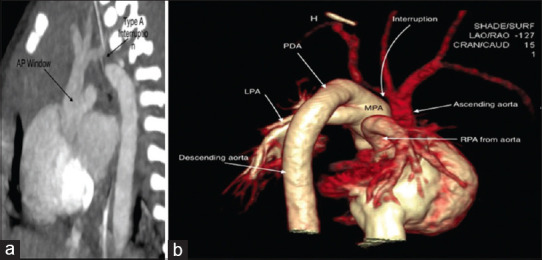

Berry et al. (1982) described a rare syndrome associated with distal aortopulmonary window, aortic origin of the right pulmonary artery, intact ventricular septum, and interruption or coarctation of the aorta. Here, we present the first neonatal case of single-stage repair of Berry syndrome in India. Timely surgery and skilled postoperative care define the short-term and long-term outcomes. Single-staged repair is preferred wherever feasible.